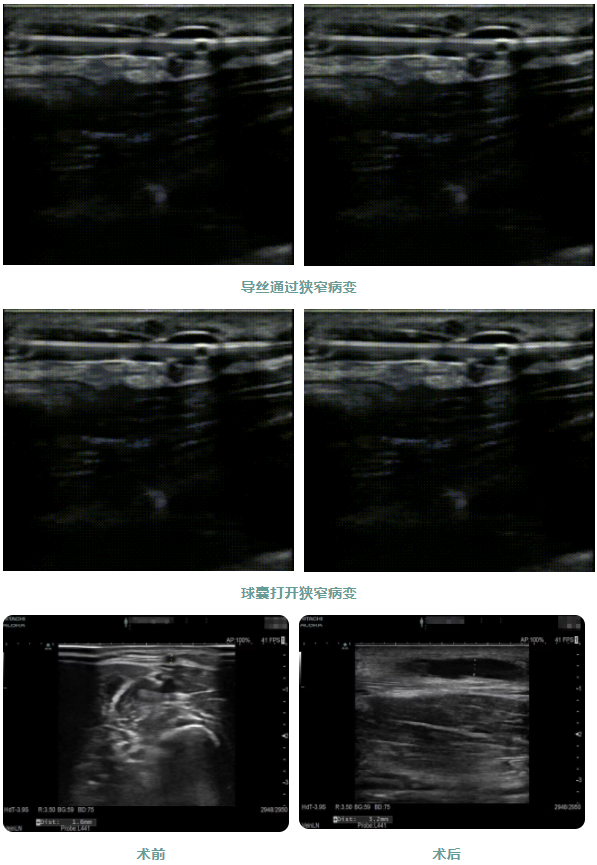

患者1年前出現(xiàn)周身乏力伴有雙下肢水腫癥狀,在外院行“為腎透析的動(dòng)靜脈造瘺術(shù)”后規(guī)律透析治療。因內(nèi)瘺無(wú)震顫2日,為求系統(tǒng)治療來(lái)院,入院后腎內(nèi)科金明花主任帶領(lǐng)醫(yī)護(hù)團(tuán)隊(duì)立即完善相關(guān)檢查,診斷為:動(dòng)靜脈內(nèi)瘺血栓形成,經(jīng)超聲檢查發(fā)現(xiàn)動(dòng)靜脈內(nèi)瘺血栓形成狹窄,最窄處內(nèi)徑約1.6mm。

為了節(jié)約患者有限的血管資源,盡早治療,經(jīng)過(guò)腎病內(nèi)科金明花主任及科室共同討論并爭(zhēng)得患者家屬同意后,決定對(duì)患者進(jìn)行超聲引導(dǎo)下動(dòng)靜脈內(nèi)瘺球囊擴(kuò)張術(shù)+血栓碎栓術(shù)解決內(nèi)瘺狹窄及血栓。手術(shù)過(guò)程中金明花主任在內(nèi)瘺狹窄位置近心端進(jìn)行穿刺,沿穿刺針置入導(dǎo)絲、置入血管鞘,在超聲實(shí)時(shí)引導(dǎo)下球囊到達(dá)病變部位,緩慢擴(kuò)張球囊,解決狹窄病變,并壓碎血栓,使內(nèi)瘺通暢。整個(gè)手術(shù)僅用30分鐘,用時(shí)少,效果明顯,術(shù)后內(nèi)瘺血管雜音及震顫明顯,手術(shù)效果立竿見(jiàn)影。